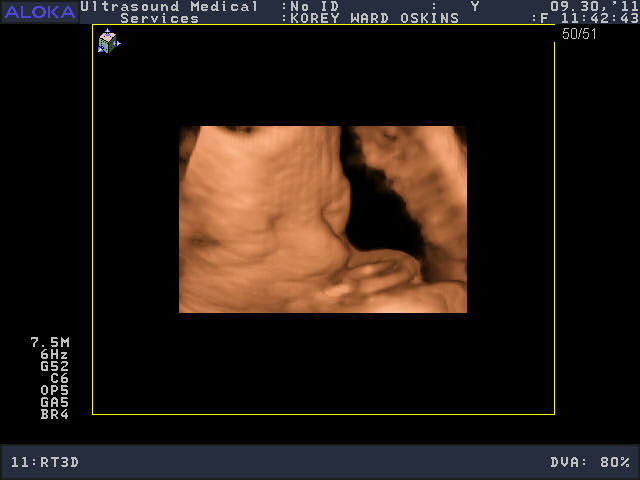

He was a very stubborn baby, so it was really kind of nerve-wracking at first thinking we might not get a single good picture. His face was squished up against the placenta and he wouldn’t budge. You’ll see that in the pictures below; it looks like an enveloping cloud or a scallop shell. Finally he moved a bit and we got some glimpses of his face. We saw him make some facial expressions, wiggle his fingers, and move his mouth around. We were curious to see whose nose he would have, and in some pictures, it looks like he has Josh’s, in others, mine.

So who do you think he looks like?

He is sooooo cute! Personally, I think he looks like ME.